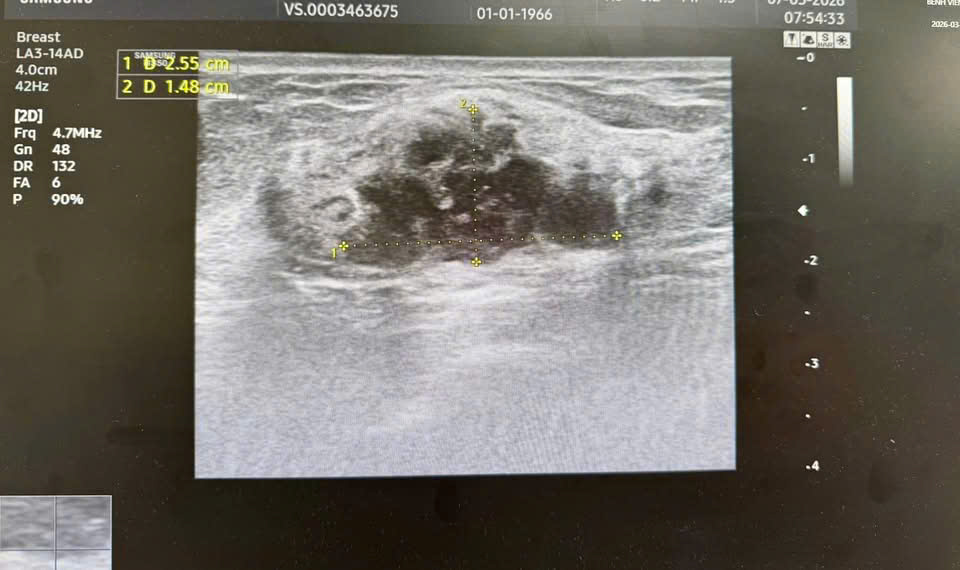

Hình ảnh khối u được phân loại BIRADS 4 trên siêu âm và chụp X-quang tuyến vú.

Kết quả siêu âm và chụp X-quang tuyến vú cho thấy hình ảnh khối u được phân loại BIRADS 4 – nhóm nghi ngờ ác tính cần làm thêm xét nghiệm. Sau đó, kết quả xét nghiệm tế bào học xác định bệnh nhân mắc ung thư biểu mô tuyến vú giai đoạn sớm.